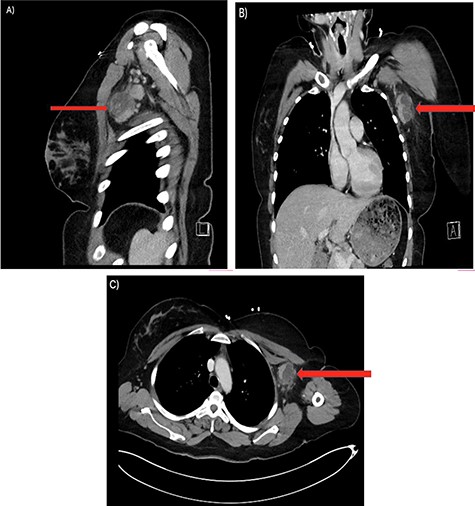

Her past surgical history included a Cesarean section and internal fixation of her left tibia. Her family history was unremarkable. Her vital signs were all within normal limits. The patient had no significant abnormalities with her routine labs within normal limits except for an elevated WBC count of 18 200 cells/ml. She was tested negative for STIs. The CT scan (Fig. 1) identified multiple enhancing soft tissue lesions involving the left axilla, with the largest lesion demonstrating internal necrosis and adjacent infiltrative changes, while the right axilla was unremarkable. The initial differential included neoplastic, metastatic, infectious or inflammatory processes. General surgery was consulted to rule out an abscess. Discussion was held with the patient about excisional biopsy of the lesion. She had excision of the left axillary mass. The pathology report confirmed the diagnosis of necrotizing histiocytic lymphadenitis (KFD) with focal necrosis devoid of neutrophils in the lymph node (Figs 2–5).

There are multiple enhancing soft tissue lesions involving the left axilla, the largest measuring 4.0 × 3.5 × 4.3 cm and 2.3 × 2.2 × 2.3 cm in maximal AP (A), Sagittal (B) and Coronal (C) Axial, with the largest lesion demonstrating internal necrosis and adjacent infiltrative changes.